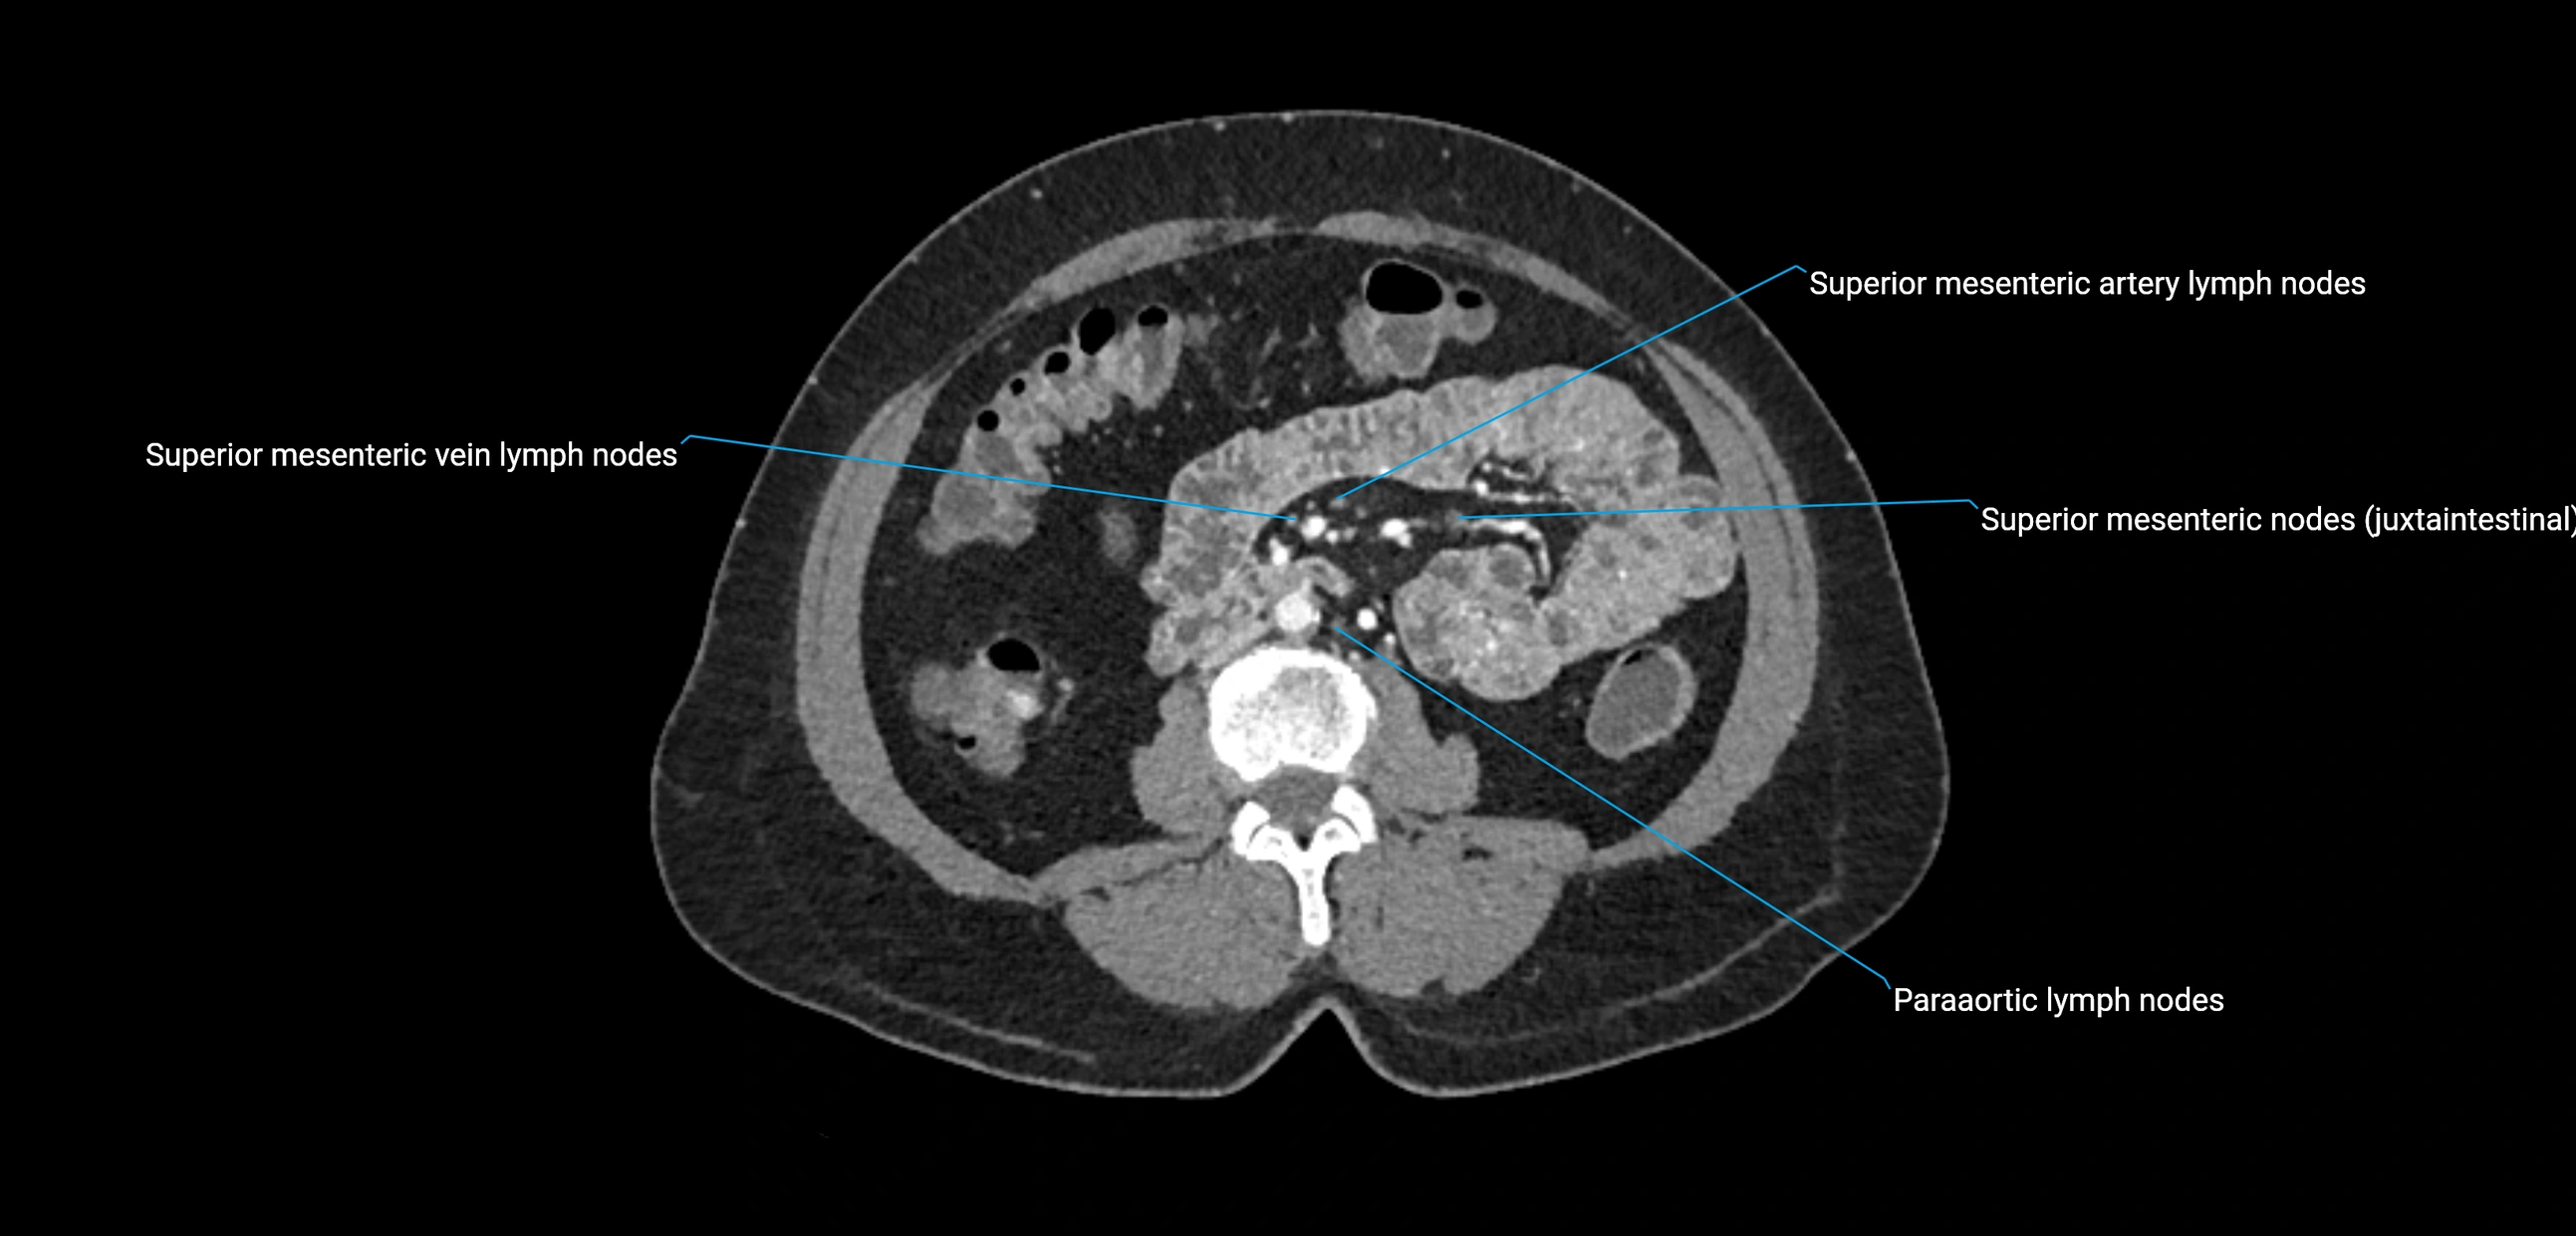

The lateral aortic lymph nodes (also called para-aortic lymph nodes) are a major group of retroperitoneal lymph nodes located along the abdominal aorta and its branches. They lie between the diaphragmatic crura superiorly and the bifurcation of the aorta at L4 inferiorly.

They are positioned on both sides of the abdominal aorta:

• Right lateral aortic nodes: adjacent to the inferior vena cava (IVC)

• Left lateral aortic nodes: lateral to the abdominal aorta

These nodes receive lymph from a wide range of abdominal and pelvic structures. Specifically, they drain lymph from the kidneys, suprarenal glands, gonads (testes/ovaries), uterus, uterine tubes, and pelvic organs, before converging into the lumbar lymphatic trunks, which terminate in the cisterna chyli → thoracic duct.

CT Appearance

CT Post-Contrast:

• Normal nodes enhance homogeneously

• Malignant nodes may show heterogeneous enhancement, central necrosis, or conglomerate formation

• Size >1 cm short axis is suspicious, though morphology and distribution are equally important